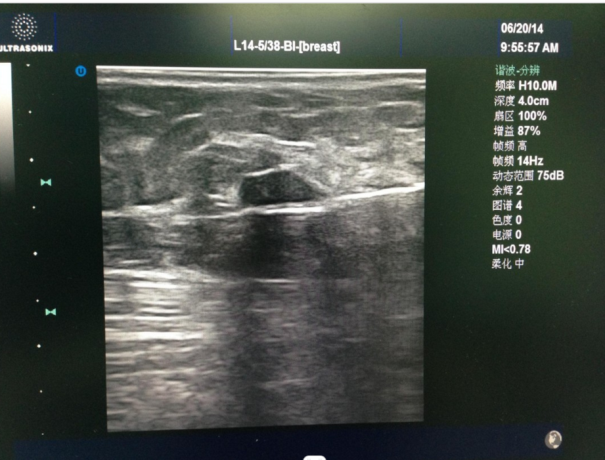

▲彩超引導(dǎo)下穿刺旋切腫塊